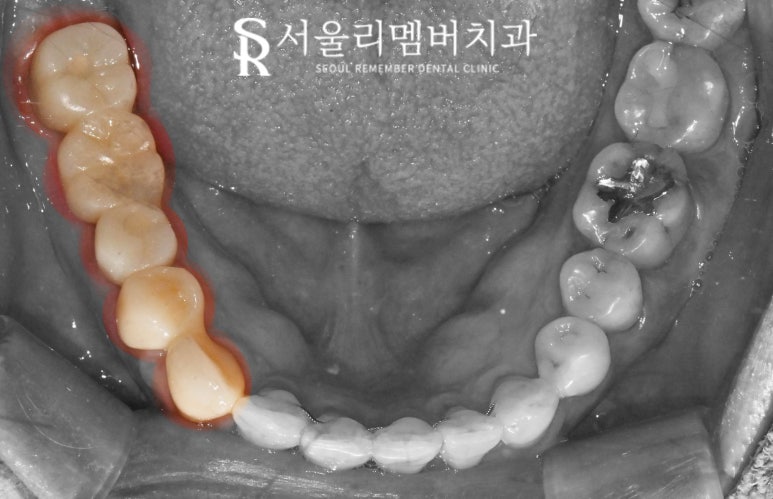

먼저 입안을 보면

오른쪽 아래 구치부에 다수의

문제가 생겨있습니다.

*이해를 돕기 위해

세가지 색으로 구분하여

설명드리겠습니다.

순서대로 살펴보면

먼저 43번과 44번 치아는

오래된 보철로 덮여있으나

음식이 자주 끼면서

주변 잇몸이 붓고,

그 뒤 45번부터 47번까지는

오래된 브릿지가 닳아서

내부 금속이 비쳐 보이고 있습니다.

또한 맨 뒤에는 사랑니가 자리 잡고

있는데요,

구강 내 제일 뒤쪽이라

잘 보이지는 않으나

교합면에 충치가 생겨있는 것을

확인할 수 있습니다.